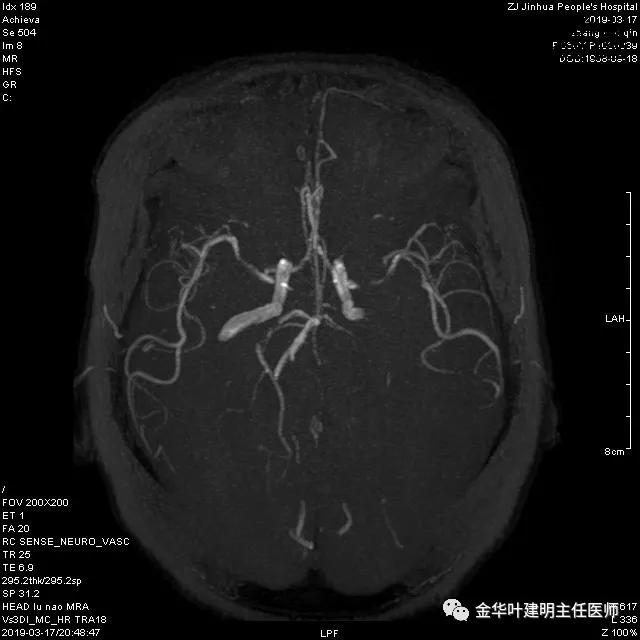

章某有高血压病史多年,平时血压控制的也不规范。术前我们予以控制血压,并常规检查头颅MRA,结果却发现了意外的合并问题:

报告提示左侧大脑中动脉M1段及左侧大脑后动脉P1段管腔闭塞。按影像科的建议并请神经内科会诊后,予以行CTA检查。结果如下:

可见其左侧大脑中动脉起始部管腔重度狭窄,右侧大脑中动脉近段管腔也有狭窄;左侧大脑后动脉中远段未见显影。又建议其DSA检查。我们仔细询问章某平时没有神经系统的症状,回忆起来说大概3年前有段时间头昏比较明显,但也没有到大的医院详细检查,后来自行改善。鉴于平时并无明显症状,我们认为其脑血管的病变是慢性闭塞,并已经有侧支代偿。便先请神经外科会诊,会诊后的意见是可以先处理肺部疾病,待情况稳定后再到神经外科进一步诊治。这样,我们便打算为其进行手术。当然因为上叶病灶考虑良性,且位置靠肺外周部位,而下叶病灶考虑恶性,又是中肺叶中央,无法亚肺叶切除,况且病灶大于3厘米,密度虽还是混合磨玻璃,但已经明显偏向实性。所以拟定手术方式是“胸腔镜下左肺下叶切除+上叶楔形切除及纵隔淋巴结清扫术”,当然万一上叶也是恶性,也只能同样是这样的手术方式,全肺切除显然风险过高。